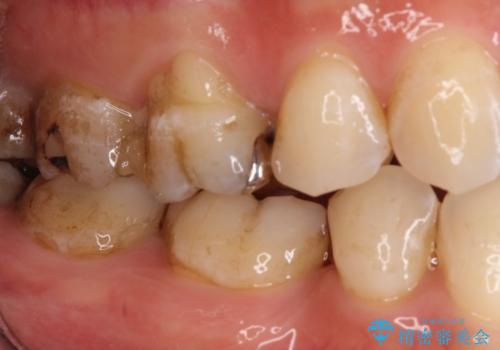

【オールセラミッククラウン】虫歯の治療

- 奥歯がかけたことを主訴に来院されました。

オールセラミッククラウンにて修復治療を行っております。

歯の破折強度を高めるためにクラウンによる修復を希望され、治療を行っております。